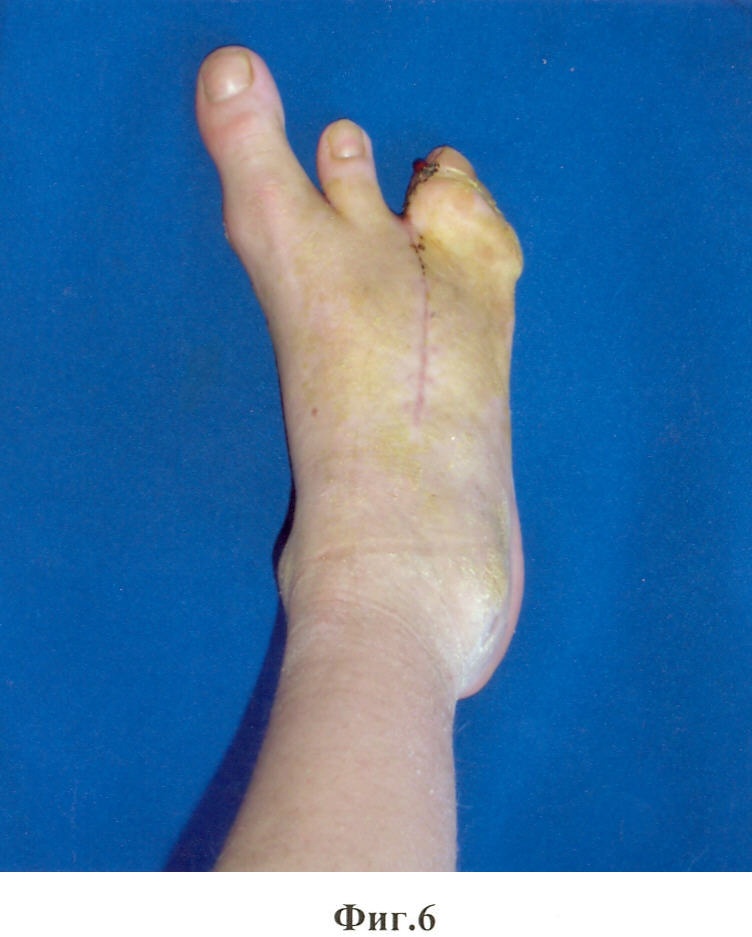

Предложенный способ иллюстрируют приведенные рентгенограммы и фотографии, где на фиг.1, 2 показан вид стопы до операции; на фиг.3, 4 – вид после операции; на фиг.5, 6 – снимок и фотография стопы через два месяца после операции.

21.12.2006 г. – больному была проведена операция по разработанной методике на правой стопе. Наркоз. Из разрезов по тыльной и подошвенной сторонам иссечены края расщелины стопы. С тыльного доступа удален III луч. Основание луча, прилегающее к II клиновидной кости, оставлено в виде костного фрагмента. Острым долотом с медиальной стороны кубовидной кости, ближе к основанию, поперечно длиннику стопы выбит костный клин, угол которого соответствует углу отклонения наружной половины расщепленной стопы от ее средней линии. Костный клин выбран так, что его вершина не доходит до наружного края кубовидной кости на 2-3 мм. Резецирован костный выступ по наружной стороне дистальной части II плюсневой кости. Через диафиз II плюсневой кости и дистальный отдел кубовидной кости поперечно с тыла на подошвенную сторону просверлены каналы. Через сформированные каналы проведена металлическая проволока так, чтобы концы ее вышли на тыл стопы. Обе половины расщепленной стопы с усилием смещены навстречу друг другу так, чтобы смежные стороны половин полностью сомкнулись. Концы проволоки с натяжением стянуты, скручены в узел и погружены в межкостную щель. Кожные швы до дренажей. Спиртовая повязка. Подошвенная гипсовая лонгета. Через две недели заживление раны первичным натяжением (фиг.3, фиг.4). Кожные швы сняты. Через 2 мес гипс снят. На контрольной рентгенограмме виден костный синостоз между фрагментом основания плюсневой кости и телом кубовидной кости (фиг.5, фиг.6). Больной начал нагружать правую стопу.

Таким образом, предлагаемый способ устранения сложного врожденного расщепления стопы позволяет восстановить нормальную форму и функцию стопы, сократить сроки лечения, исключить опасность спицевой инфекции. Результатом проделанной операции пациент доволен, он получил возможность носить обычную обувь.